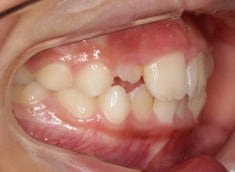

症例紹介

小児期ケース:叢生(ガタガタ)

治療法:拡大プレート+フルパッシブブラケット(クリアスナップ)

治療前